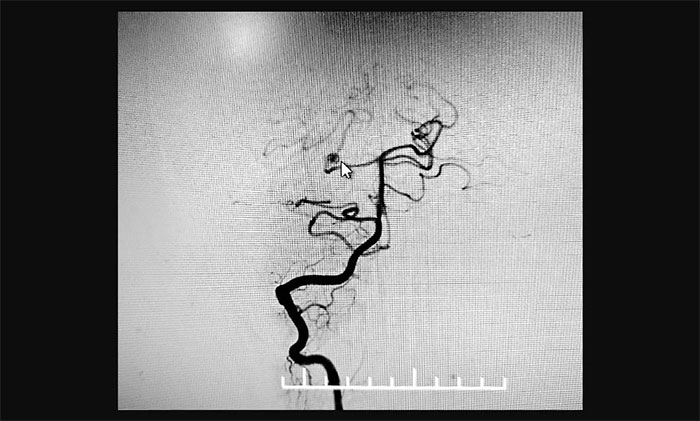

最終,在麻醉科團(tuán)隊(duì)及導(dǎo)管室介入團(tuán)隊(duì)的密切配合和監(jiān)護(hù)下,神經(jīng)外科于耀宇主任團(tuán)隊(duì)歷時(shí)2小時(shí),為王女士順利實(shí)施腦血管造影+顱內(nèi)動(dòng)脈瘤栓塞術(shù)。術(shù)中,DSA造影確診右側(cè)小腦上動(dòng)脈夾層動(dòng)脈瘤,動(dòng)脈瘤瘤體大小約為4x3 mm。術(shù)中,于耀宇主任憑借嫻熟的技術(shù),克服血管迂曲等困難,將栓塞導(dǎo)管成功送入夾層動(dòng)脈瘤內(nèi),最終順利栓塞夾層動(dòng)脈瘤。術(shù)后,再次造影未見動(dòng)脈瘤顯影,見遠(yuǎn)端分支顯影良好,“炸彈”危險(xiǎn)被成功解除。術(shù)后,患者順利蘇醒,無神經(jīng)功能障礙。

▲ 栓塞前